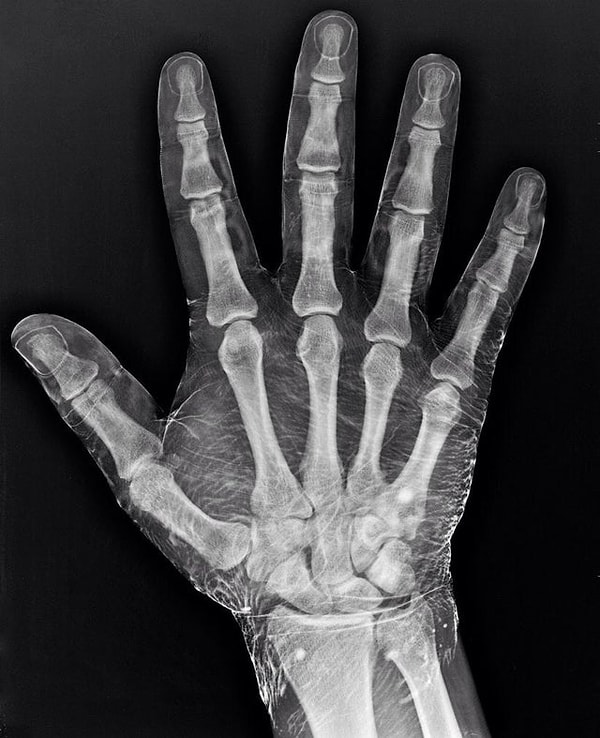

3. Так будет выглядеть рентгеновский снимок руки, на которую нанесён йод

Так как йод поглощает рентгеновские лучи, на снимке видны не только кости, но и кожа.